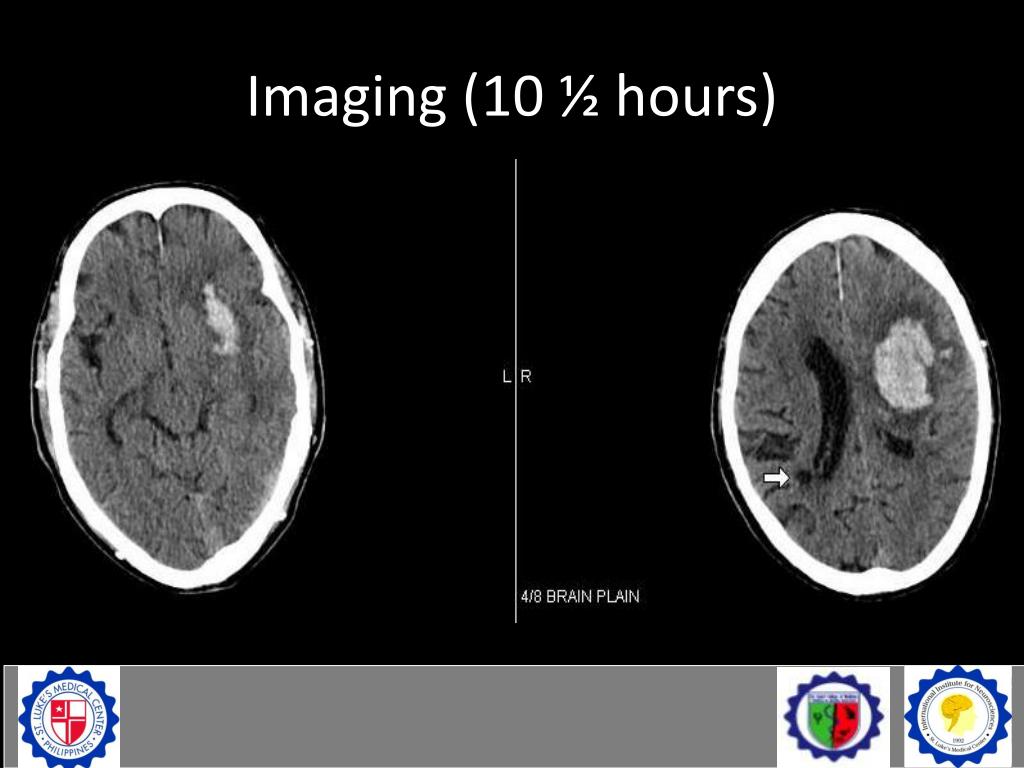

14. Imaging (10 ½ hours)

15. Imaging (10 ½ hours)

16. Imaging (10 ½ hours) • L capsuloganglionic acute intraparenchymal hematoma (42cc) • Surrounding edema • Compression of the ipsilateral ventricle and slight midline shift to the right